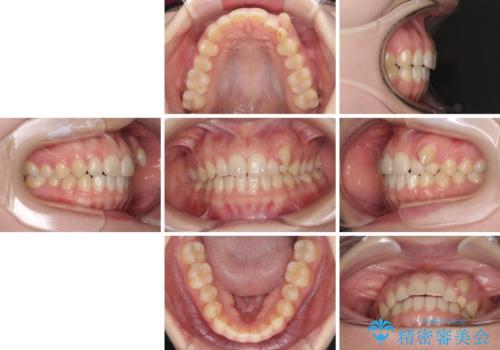

- 八重歯を気にして来院された患者様です。

八重歯のために乳歯が残存していたため、乳歯を抜去して八重歯となっている犬歯を歯列に収めることとしました。

八重歯の移動量が多くなるため、インビザラインと併用してワイヤー矯正を行い、八重歯を改善した後に、上下歯列をインビザラインで整えることとしました。

犬歯は歯根が長くて太いため移動に時間がかかる上に、周囲の歯が八重歯に寄ってきてしまうため、仕上がるまでに期間がかかりました。